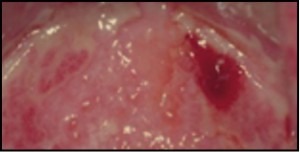

Como se ha indicado, los melanomas derivan de los melanocitos, fundamentalmente de aquellos localizados en la unión dermoepidérmica; en general, es más común en partes descubiertas de la piel y en personas inmunosuprimidas. Aunque más del 95% de los casos de melanoma tienen localización cutánea, no se considera un cáncer exclusivamente cutáneo ya que puede aparecer en ojo, mucosas, tracto gastrointestinal, tracto urogenital, meninges y nódulos linfáticos. En cualquier caso, el melanoma es el tumor maligno cutáneo más importante en razón de su pronóstico, ya que es el responsable de la mayoría de las muertes asociadas a cánceres cutáneos. La mayoría se origina de novo y otras veces aparece sobre nevos melanocíticos preexistentes.

- Melanoma acrolentiginoso y mucoso. Es más frecuente en las personas de raza negra, apareciendo en palmas, plantas, región subungueal y en mucosas. Es una mácula amplia, de coloración desigual y bordes irregulares, en cuya superficie se pueden encontrar lesiones papulosas o tuberosas.